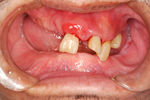

術前

術後

術中

骨を作っている途中

40才代 男性

総額:99万円(税別)

治療期間:6ヵ月

リスク副作用:上顎洞の炎症。インプラント体の迷入。セラミッククラウンの破損。